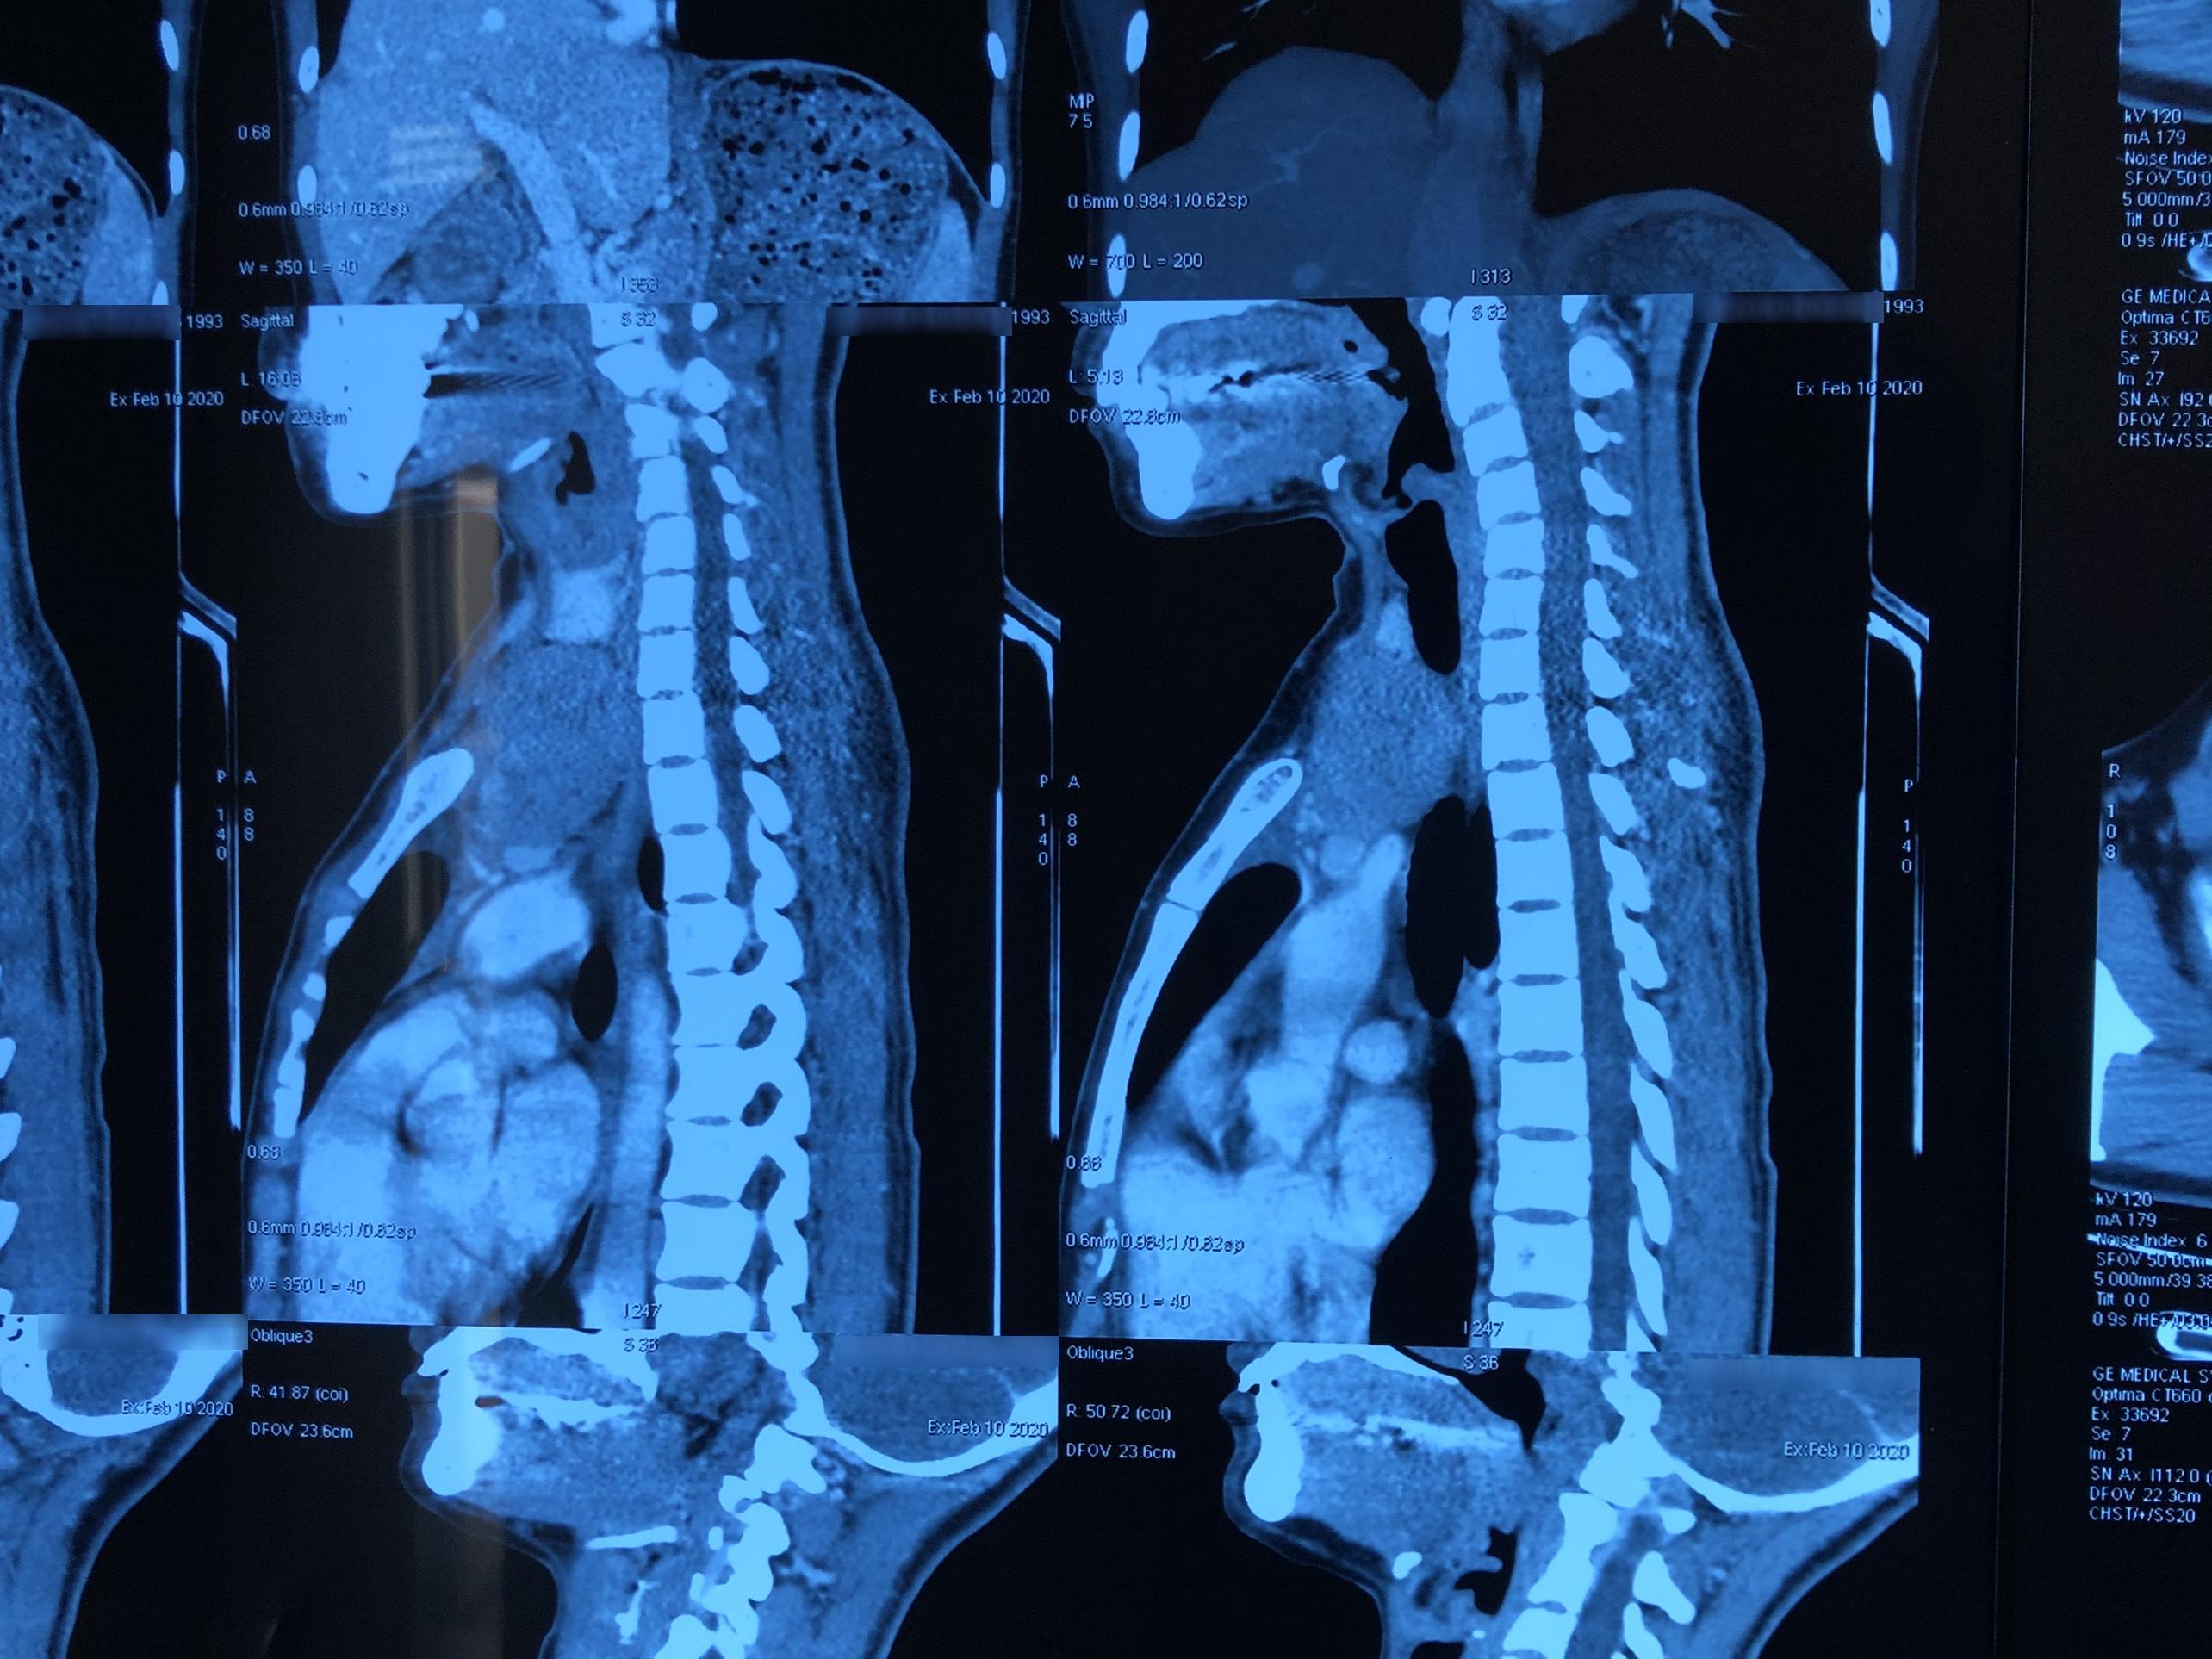

Hình ảnh phim chụp khối u tuyến ức lạc chỗ

Thấy cổ to lên bất thường, chị N.T.H., sinh năm 1993, trú tại Cẩm Khê, Phú Thọ liền đến Bệnh viện Ung Bướu Hà Nội để kiểm tra. Qua thăm khám ban đầu, nghi ngờ có u giáp trái. Bệnh nhân được chỉ định chụp cắt lớp 64 dãy vùng cổ kết hợp sinh thiết kim. Kết quả giải phẫu bệnh và chẩn đoán hình ảnh xác định là u tuyến ức typ AB tại vị trí trung thất trước trên và một phần vùng cổ trái kích thước 8x5cm hay còn gọi là u tuyến ức lạc chỗ.